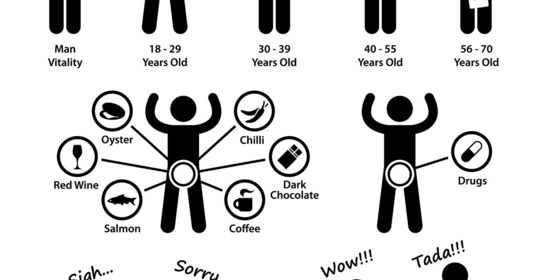

雄激素過多:維護男性荷爾蒙平衡的小秘訣!

雄激素過少的影響及調理方法,男性健康的小撇步!

血睪酮降低:男性健康問題及潛在治療方法